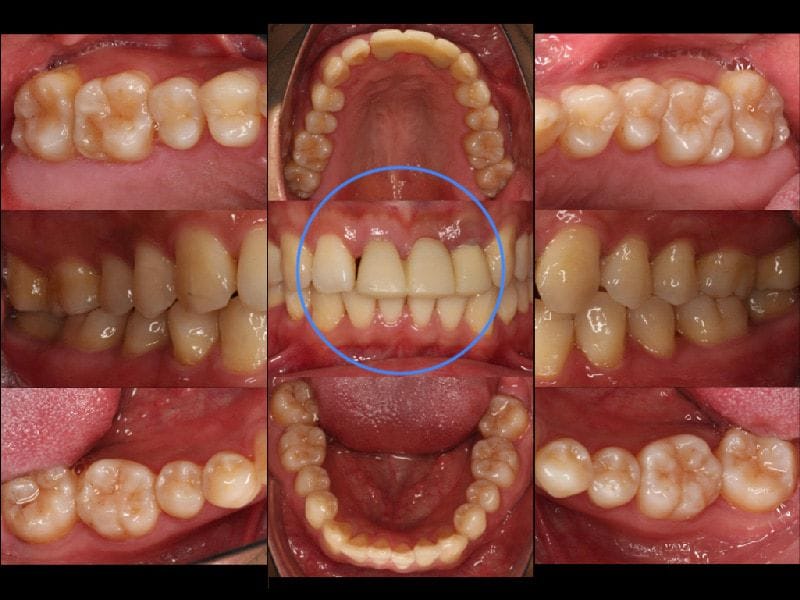

治療前完整口內檢查,其中前牙區已經更換為臨時假牙

從口內和 X 光片的檢查發現,Mr.Wang 的全口牙周的狀況還算健康,大部分的牙周齒槽骨流失不到 15 %,但是還剩下三顆阻生智齒,右上第二大臼齒的後方也有局部的嚴重牙周病。牙周相關的診斷是:全口輕度、局部嚴重慢性牙周病。